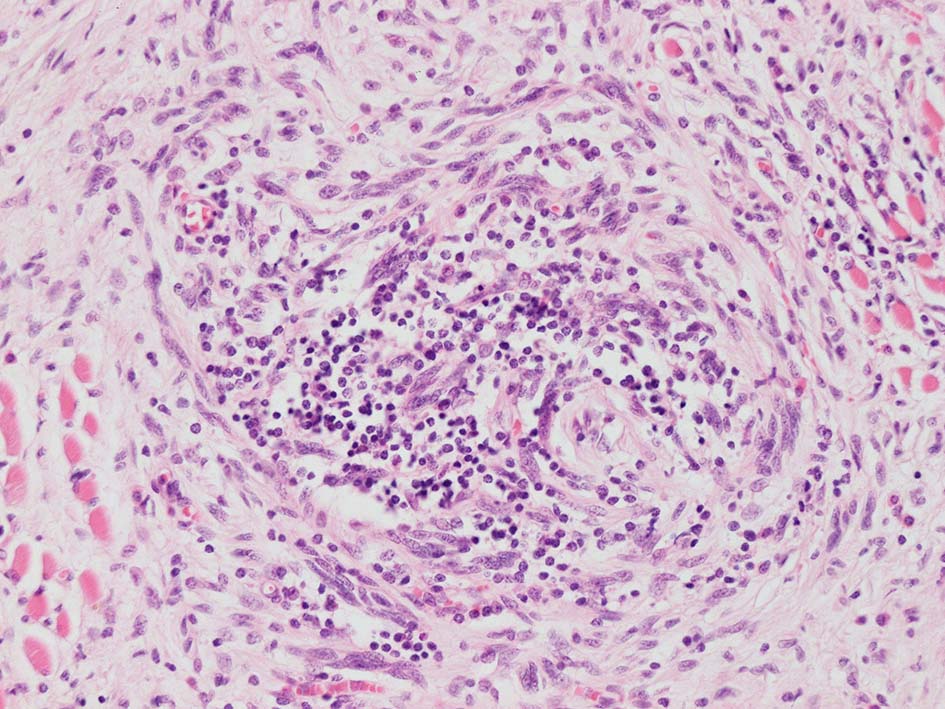

紡錘形異型メラノサイトが著明な間質反応(desmoplasia)を伴い増殖する特殊な色素性病変。*1. desmoplastic neurotropic melanomaは, desmoplastic melanomaのうち神経向性(neurotropism:神経周囲侵襲像)がめだつものでReedら*2が最初に報告した。

いずれも腫瘍細胞の異型性が乏しく, 背景の間質反応がめだつこと, メラニンの存在が目立たないことが特徴である。

リンパ濾胞が細血管周囲に形成され, この部分に異型といえる細胞が増加している(S100+)

再発腫瘤病変の組織像